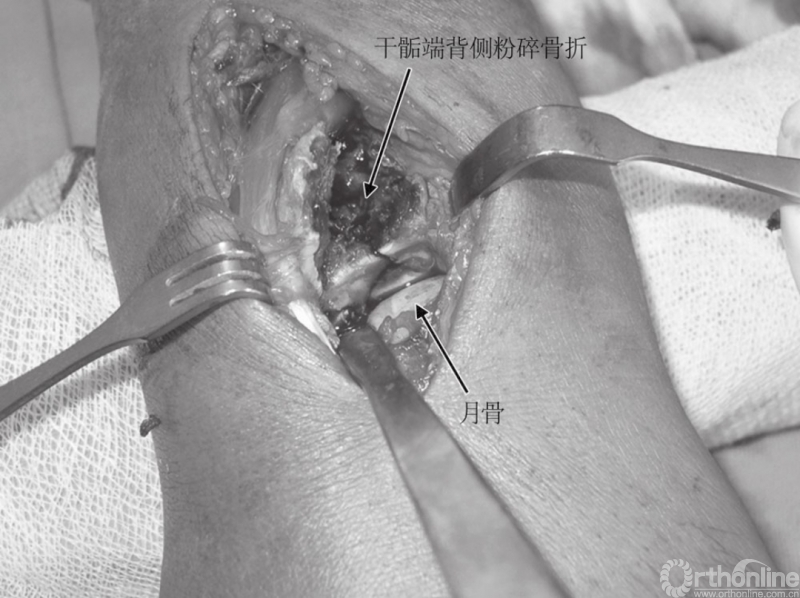

另做一切口进入第二伸肌间室,在直视下复位侧柱。从桡骨茎突上松解肱桡肌腱有助于内固定的植入,并可缓和茎突上肌肉的变形力。背侧入路显露过程中唯一有损伤风险的血管神经结构是桡神经浅支,在第二间室切开时应注意探查并保护。以月骨、舟骨为参照物,直视下复位关节面,并在尽可能的远端、软骨下骨打入1mm克氏针做临时固定。

图6 术中见关节面